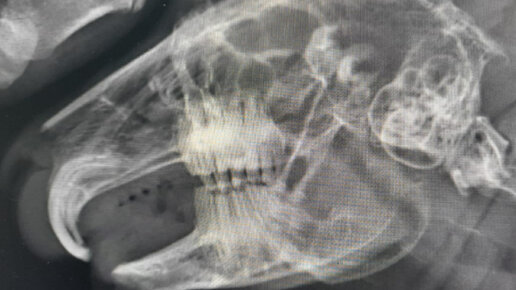

С кроликом по кличке Боб мы вас уже знакомили, малыш часто приходил в ветеринарную клинику в Калуге "Жизнь" на коррекцию резцов. В последнее время промежутки между подрезаниями резцов уменьшились, поэтому наши специалисты решили провести Бобу удаление резцов...